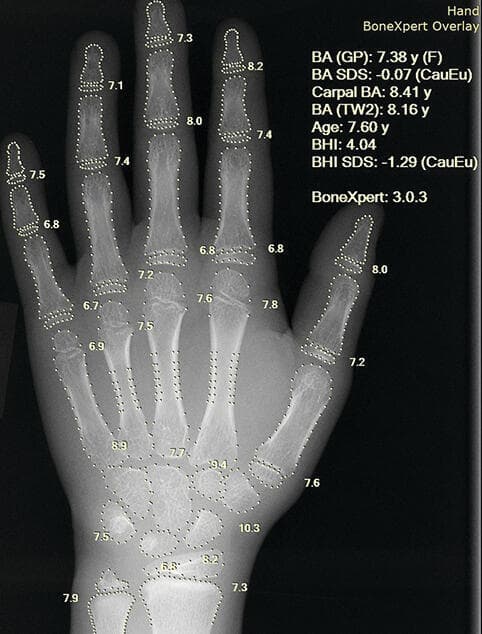

תוצאות מיידיות: מערכת AI לבדיקת הערכת גיל עצם, בדיקה חשובה במיוחד למעקב אחרי ילדים שסובלים מעיכוב בגדילה